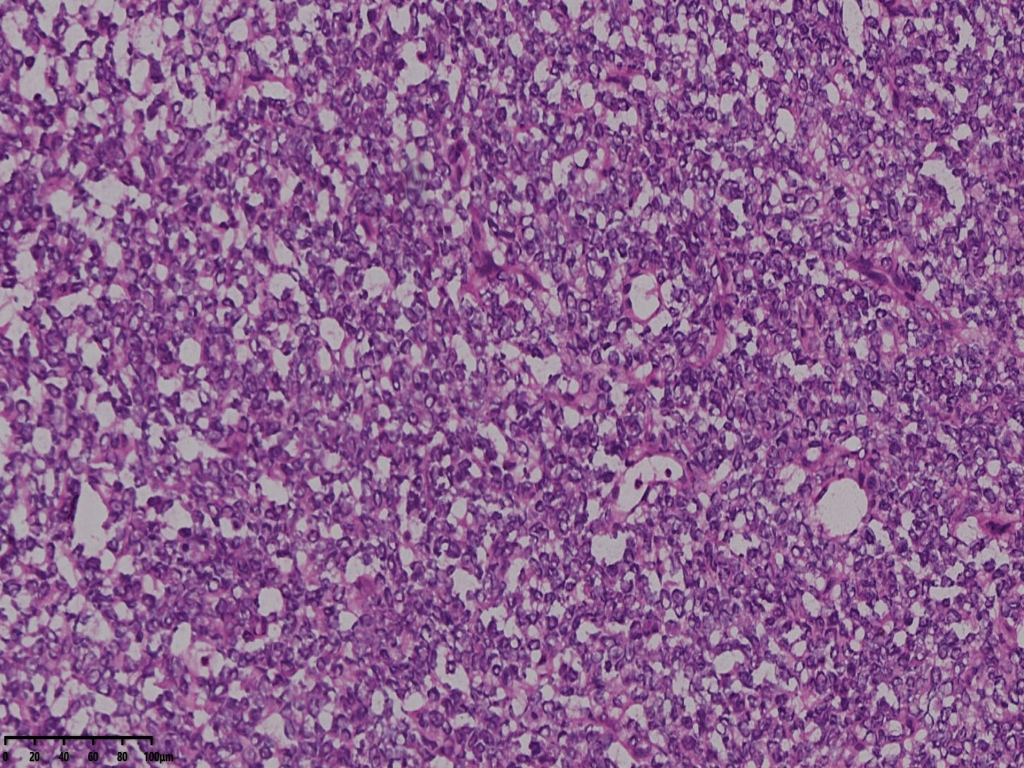

冰冻切片取两块实性区组织,其中1块可见梭形细胞为主,另一块似上皮样细胞,细胞丰富密集。

术中考虑卵巢性索间质来源肿瘤,待石蜡及免疫组化。

考虑颗粒细胞瘤。